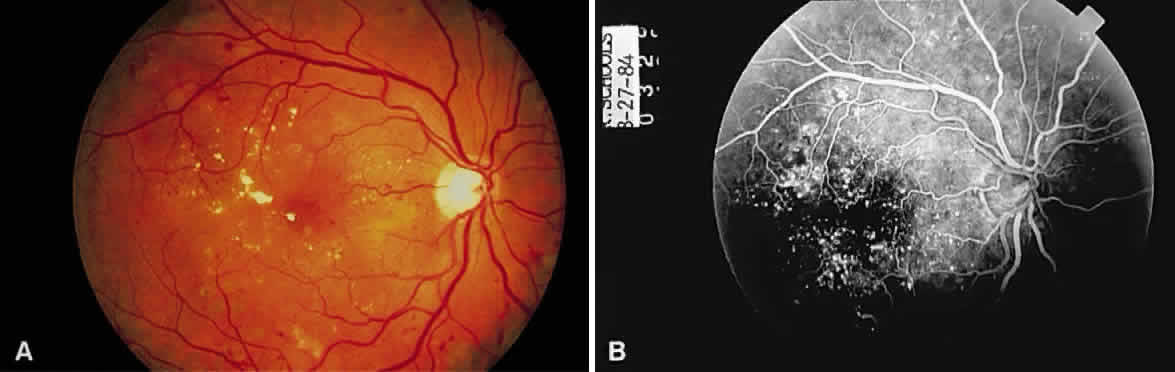

Fig. 13. A. Fundus photograph of a subpigment epithelium hemorrhage superotemporal

to the disc secondary to a macroaneurysm. Notice its dark color and sharp

border. The central portion of the hemorrhage has extended through

the sensory retinal to the subinternal limiting membrane area. B. Fluorescein angiography showing the retinal vessels overlying the deep

hemorrhage but obscured by the central extension anteriorly. (B, courtesy of William Tasman, MD, Philadelphia, PA) Fig. 13. A. Fundus photograph of a subpigment epithelium hemorrhage superotemporal

to the disc secondary to a macroaneurysm. Notice its dark color and sharp

border. The central portion of the hemorrhage has extended through

the sensory retinal to the subinternal limiting membrane area. B. Fluorescein angiography showing the retinal vessels overlying the deep

hemorrhage but obscured by the central extension anteriorly. (B, courtesy of William Tasman, MD, Philadelphia, PA)